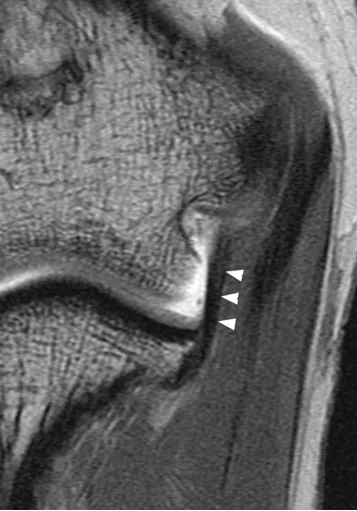

后方滑膜皱襞,是肘关节内滑膜折叠形成的结构,若受到反复刺激可能诱发炎症反应。

(a)26 岁男性受试者的横轴位质子密度加权脂肪抑制磁共振成像,以及(b)对应的示意图,均显示出后方滑膜皱襞(箭头所示)。图中 AM 代表肘肌。